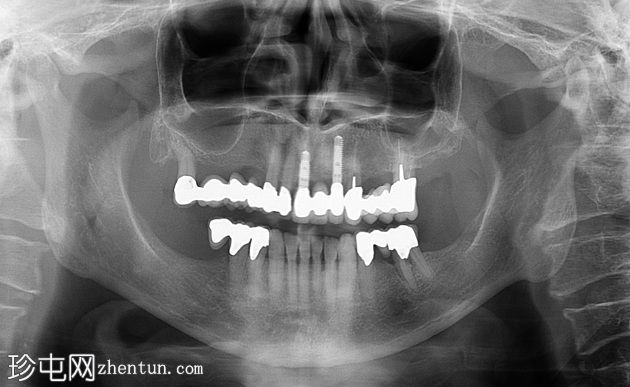

X光片

牙科全景X光片(上颌窦提升术前)

在第一和第二象限,患者出现严重的骨质流失,并接受了上颌窦提升术。